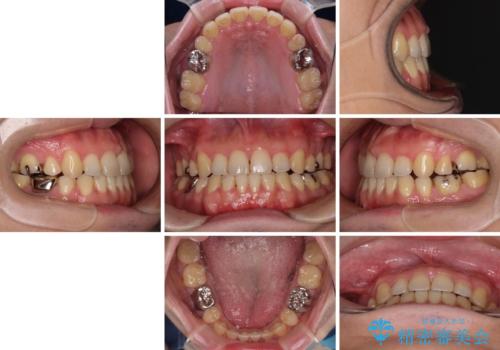

インビザラインの特性を活用して奥歯の咬み合わせを圧下させることで、前歯のオープンバイトを改善さえることができました。

- 抜歯矯正の後戻りを気にして来院された患者様です。

舌の突出癖によるオープンバイトになり、前歯の叢生が後戻りしていました。

舌のトレーニングを行いながら、インビザラインを用いて矯正治療を行うこととしました。